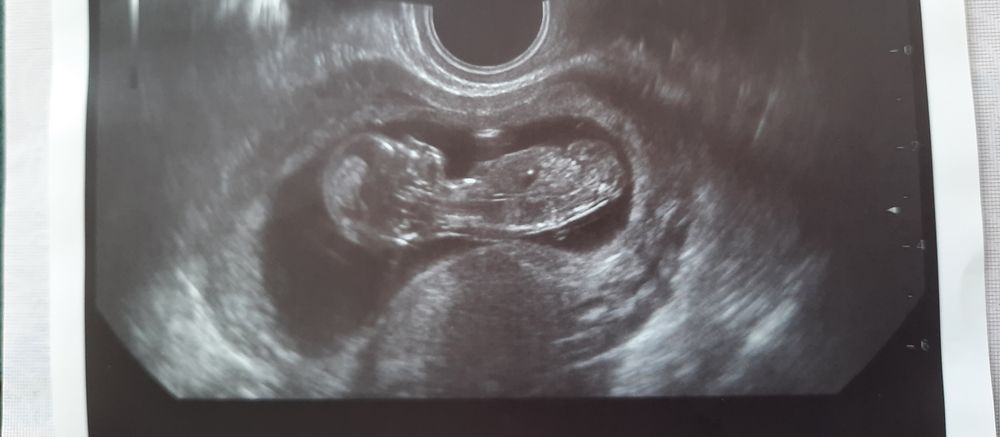

Изображение

238 хгч это нормально, если овуляция была примерно 24 июня? Получается примерно 2 недели беременности?